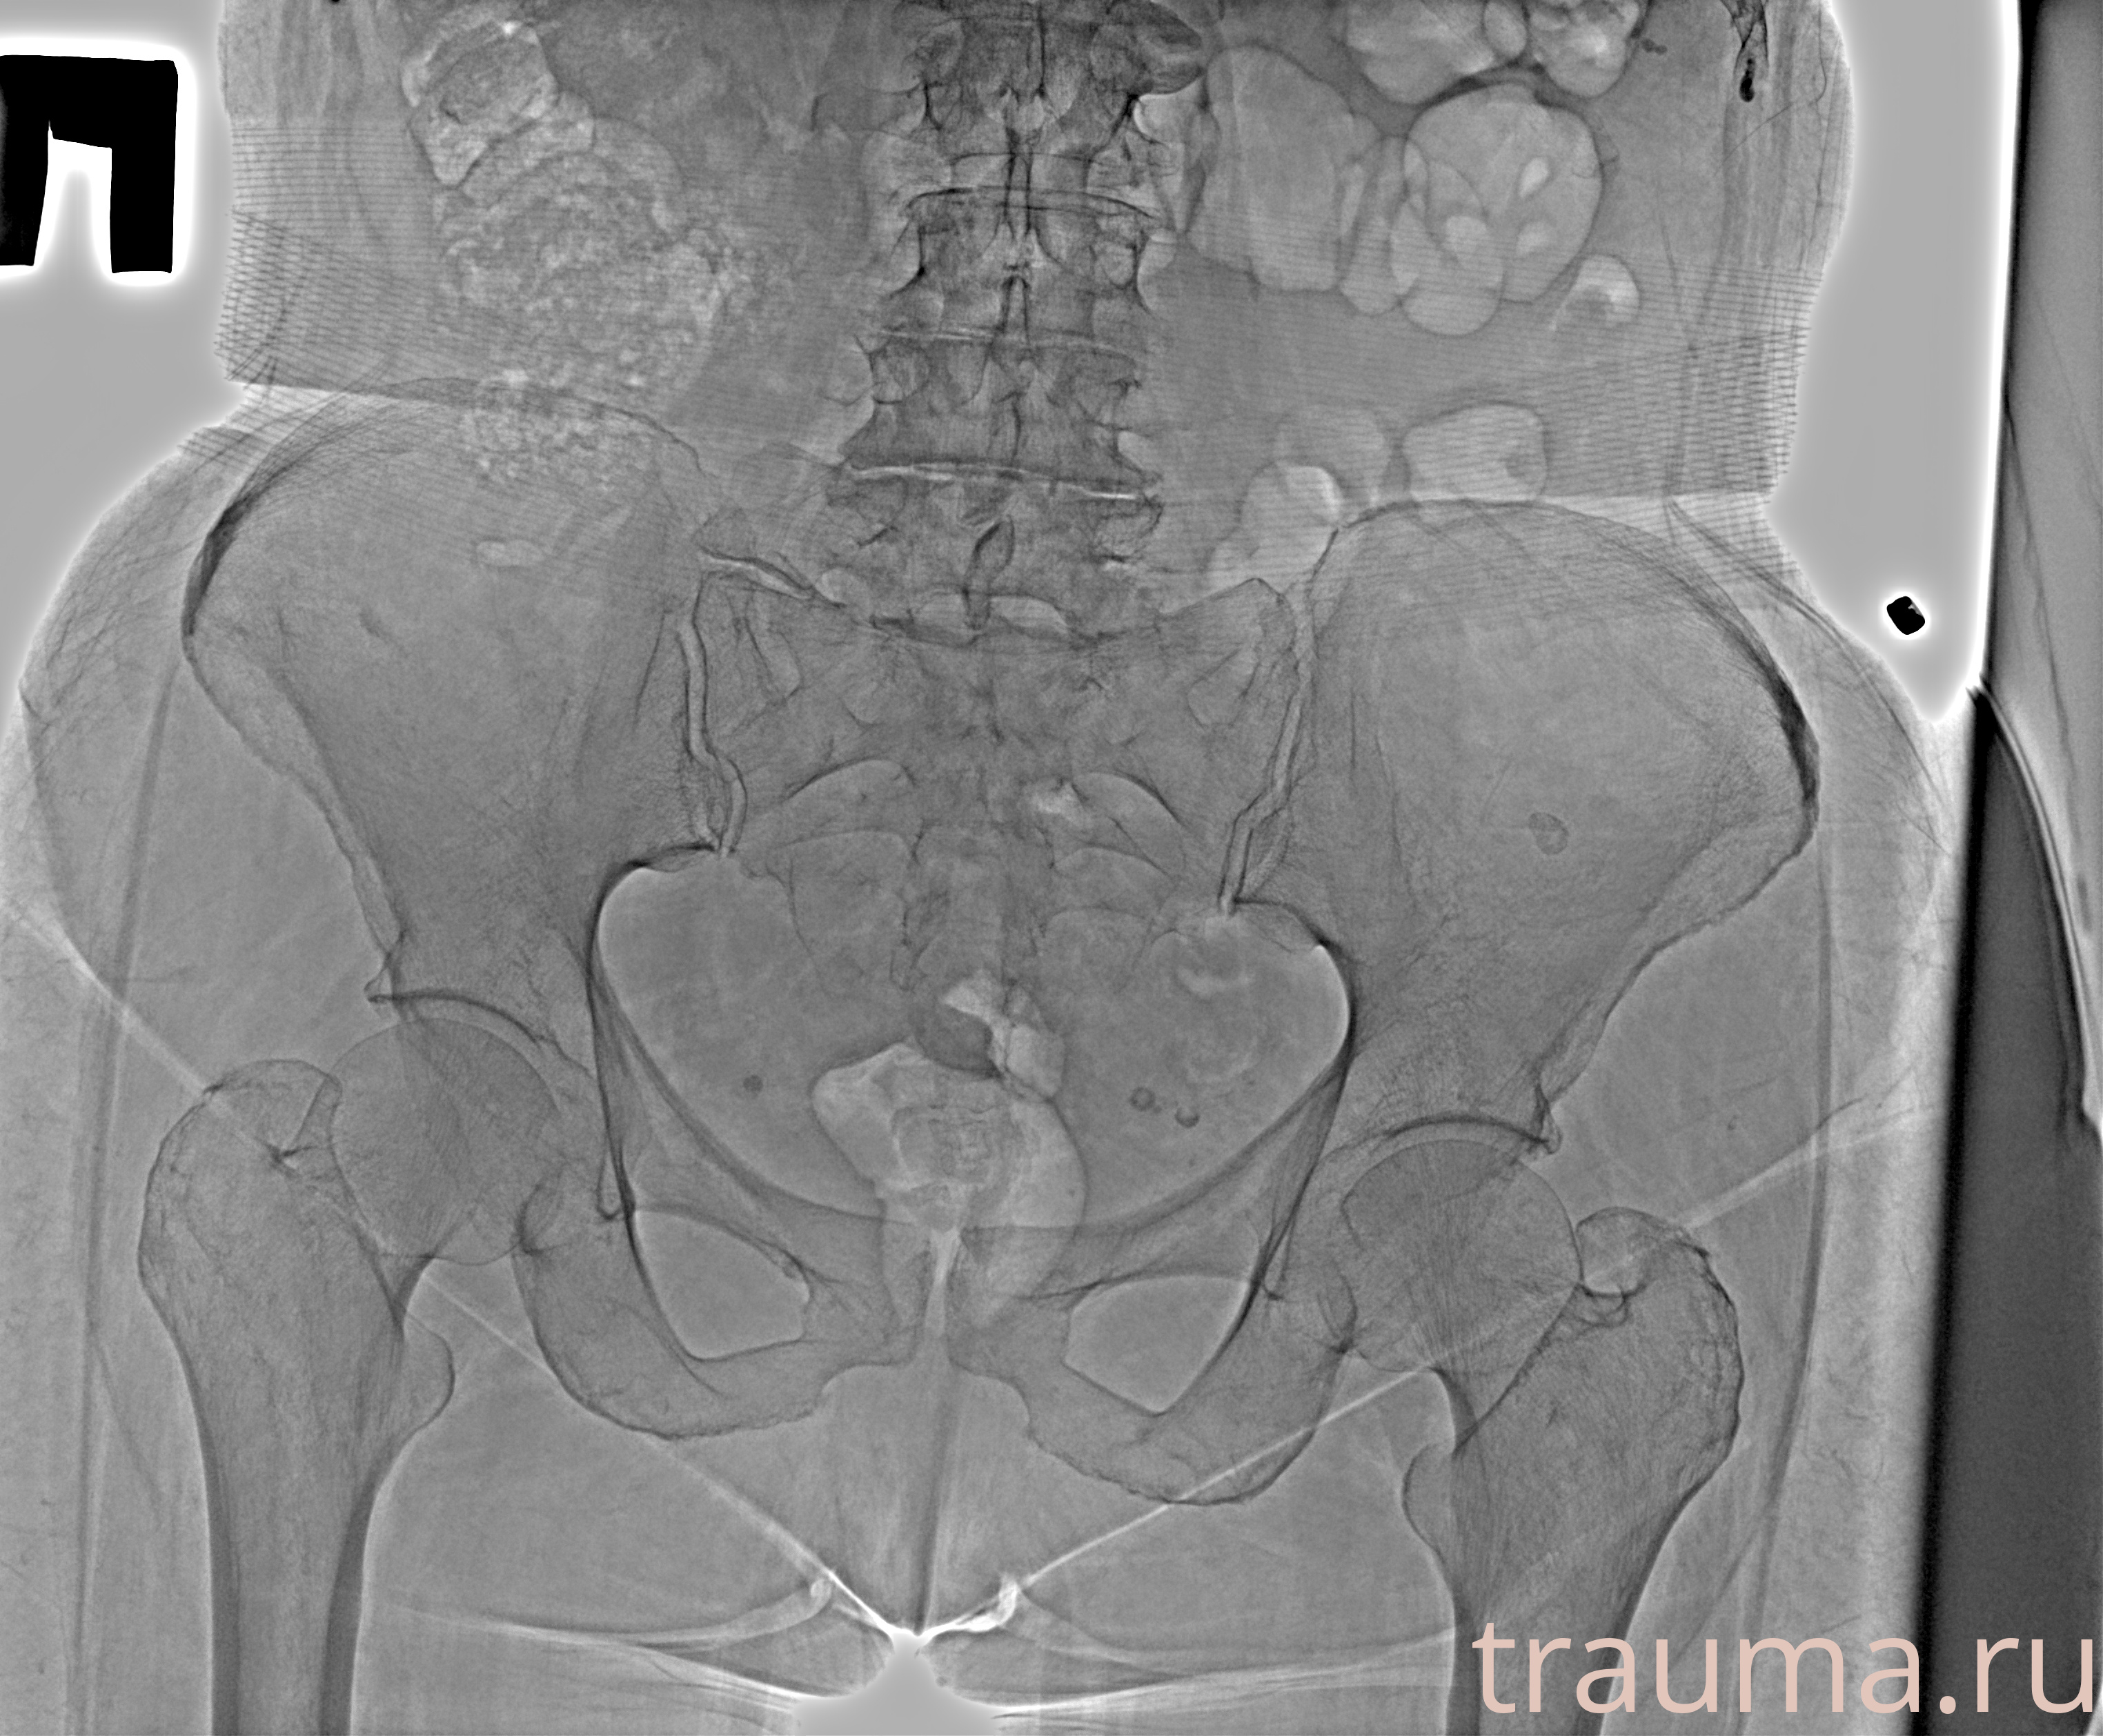

Рентгенограммы

Рентген на дому: по вашему адресу приезжает врач-рентгенолог, травматолог-ортопед с мобильным рентгеновским аппаратом, проводит диагностику травмы или заболевания, делает необходимые рентгенограммы, дает рекомендации по дальнейшему лечению. Получить качественные снимки в домашних условиях возможно благодаря уникальной методике, разработанной МосРентген Центром для института  Склифосовского

при переломе шейки бедра и пневмонии от компании МосРентген Центр - партнера Института имени Склифосовского